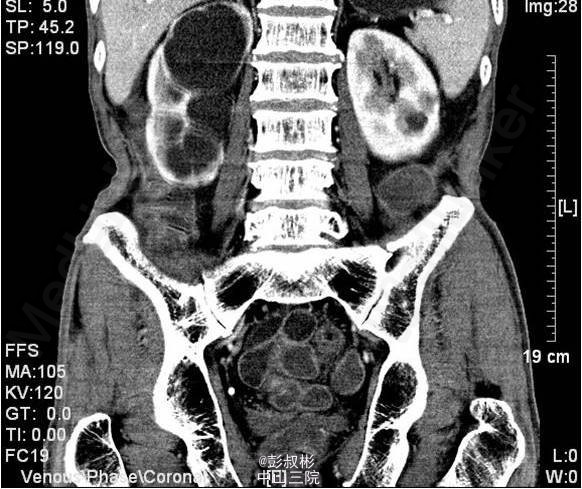

3、既往病史:既往“高血压”病史20年余,自服硝苯地平。“脑梗死”病史半年余,规律服用抗凝药物。 4、入院查体:无明显阳性体征。 实验室检查: 2015-01-11 肌酐101.2umol/L 。 2015-01-13总前列腺特异性抗原1.1ng/ml,游离前列腺特异性抗原0.3ng/ml。 2015-01-15 白细胞总数3.21x10E9/L,红细胞总数2.61x10E12/L,血红蛋白浓度78g/L,肌酐131umol/L ,白蛋白27g/L。 影像学检查: 2014-12-30心电图:完全性右束支传导阻滞。 2014-12-30全腹螺旋CT 检查所见:1、前列腺增生并钙化,建议MRI增强进一步检查除外合并肿瘤性病变。2、右侧盂管交界处结石并重度梗阻性肾积水,右肾结石;左肾多发钙化灶;左肾多发囊肿。3、慢性胆囊炎。4、双肺下叶多发小结节。 2015-01-14核素肾动态显像+GFR双血浆测定:右肾灌注、功能重度受损。左肾灌注正常,功能中度降低。肾小球滤过率:左肾为23.4ml/min,右肾为9.0ml/min。 2015-01-15彩超心脏:二尖瓣反流(轻度)。三尖瓣反流(轻度)。左室收缩功能正常。左室舒张功能减退。

5、目前诊断:1、右侧重度肾积水2、双侧肾结石3、左肾多发囊肿4、慢性胆囊炎